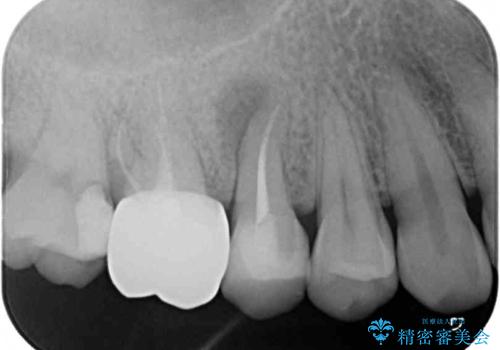

神経近くにまで及んでいる大きなむし歯や、歯肉の中深く、骨の近くにまでむし歯が進行している歯など、問題の多い状態でした。

神経を温存するための処置や、歯肉深くにまで及んだむし歯を改善するための歯周外科処置などを行っていき、オールセラミッククラウンにて補綴治療を行うこととしました。

術前の診断では神経が温存できるか否か、際どい状況でしたが、治療開始前の海外への帰省の際に自発痛(何もしなくてもズキズキ痛む)の症状が出てしまい、根管治療が必要となってしまいました。